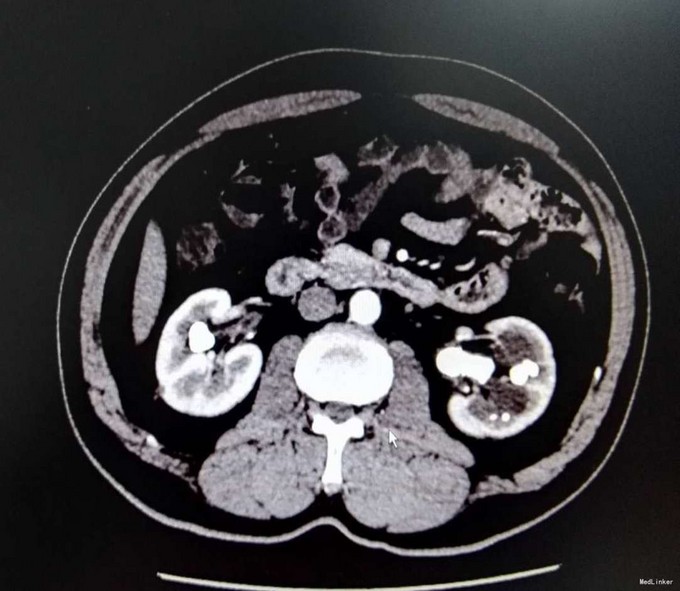

3、查体:未见明显阳性体征 4、辅助检查:外院平片:双肾多发结石;我院CTU:双肾多发结石,左侧肾盂输尿管连接处结石,并双肾积水,左肾明显,双侧肾盂、输尿管炎症。

5、诊断:肾结石(双肾多发结石) 6、治疗:入院后完善相关检查,双肾CTU:双肾多发结石,左侧肾盂输尿管连接处结石,并双肾积水,左肾明显,双侧肾盂、输尿管炎症。排除手术禁忌症后行左侧PCNL术,术后恢复良好,拔出肾造瘘管后,先出院休息,2周后返院进一步治疗